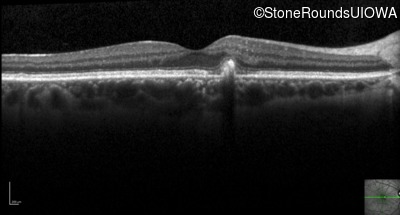

Optical Coherence Tomography - Left - 20/25 +1 sc

Exemplar / OCT Stack